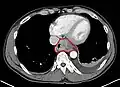

Although an occlusive tumor may be suspected on a barium swallow or barium meal, the diagnosis is best made with an examination using an endoscope. This involves the passing of a flexible tube with a light and camera down the esophagus and examining the wall, and is called an esophagogastroduodenoscopy. Biopsies taken of suspicious lesions are then examined histologically for signs of malignancy.

Additional testing is needed to assess how much the cancer has spread (see § Staging, below). Computed tomography (CT) of the chest, abdomen and pelvis can evaluate whether the cancer has spread to adjacent tissues or distant organs (especially liver and lymph nodes). The sensitivity of a CT scan is limited by its ability to detect masses (e.g. enlarged lymph nodes or involved organs) generally larger than 1 cm.[44][45] Positron emission tomography is also used to estimate the extent of the disease and is regarded as more precise than CT alone.[46] PET/MR as a novel modality has shown promising results in preoperative staging with fair feasibility and good correlation in comparison to PET/CT. It can enhance tissue differentiation with lowering the radiation dose to the patient.[47] Esophageal endoscopic ultrasound can provide staging information regarding the level of tumor invasion, and possible spread to regional lymph nodes.

Contrast CT scan showing an esophageal tumor (axial view)

Contrast CT scan showing an esophageal tumor (coronal view)